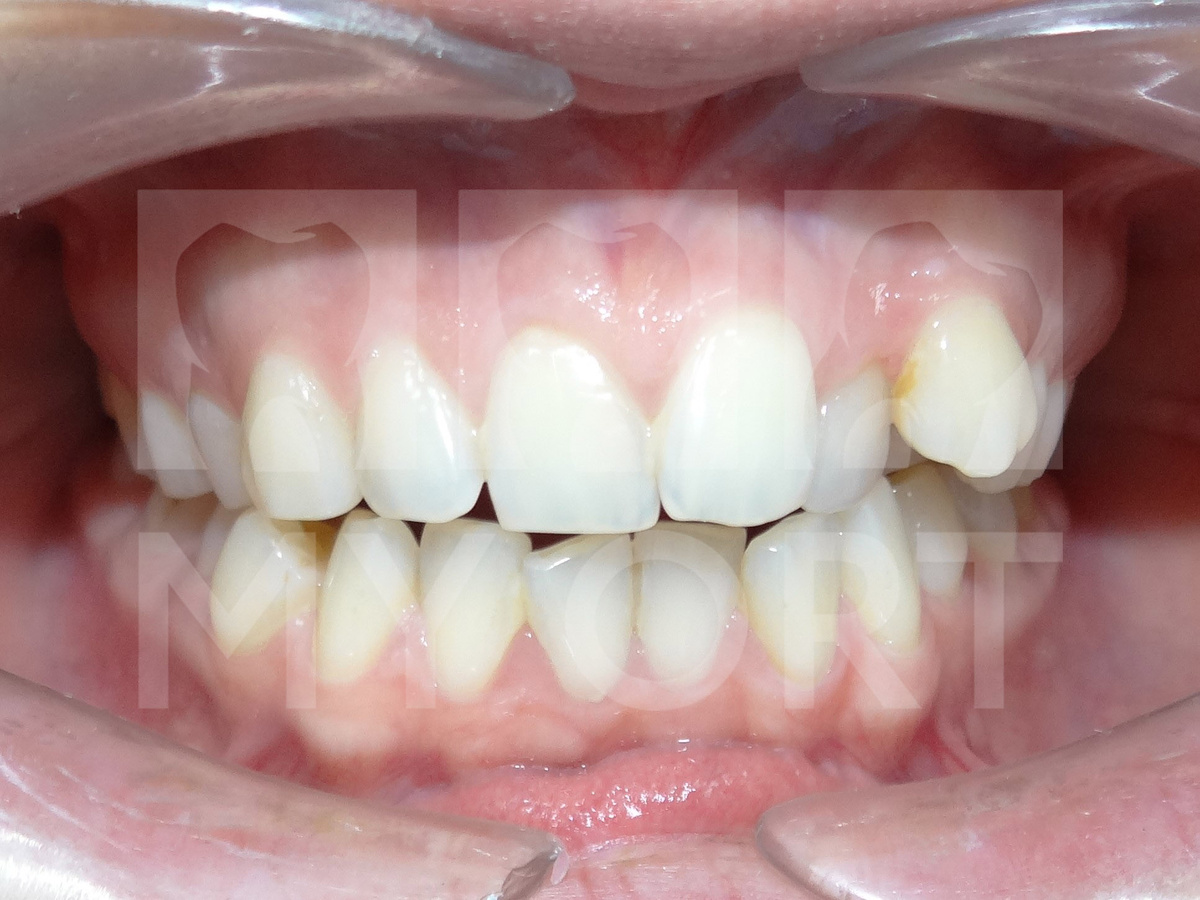

При осмотре полости рта и после проведения полной диагностики были определены нарушения прикуса: дистальный и открытый прикус. Присутствовало смещение клыков и других зубов.

ДО лечения